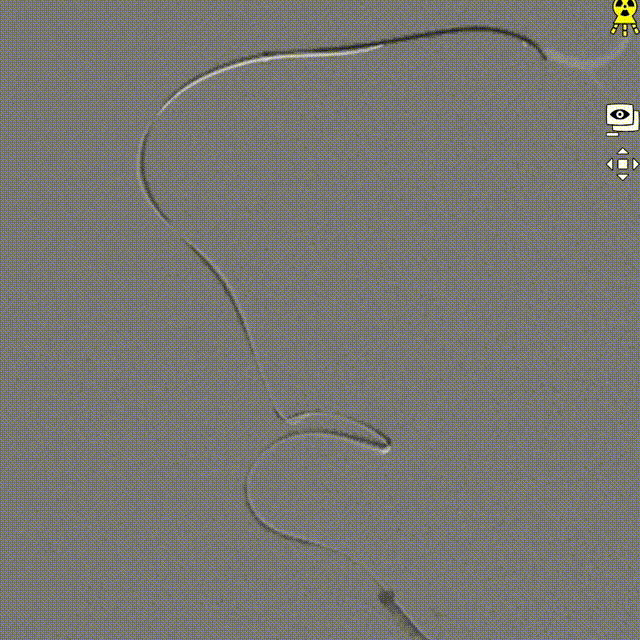

微导管到位。

交换FLOPPY导丝,提高支撑力,带高中间导管。

输送球囊到位、充盈及泄压。

撤出球囊后造影。

支架微导管到位。

支架到位。

支架全段打开。

支架全段打开造影。

回撤推送导丝及微导管。

术后造影。

术后正侧位造影。

强易达(Choydar)血流导向密网支架材质是镍钛合金,输送易到位;头端导丝、50%释放点、100%释放点清晰,便于观察支架位置。

50%Mark点可帮助分析后半段打开后的尾端位置,近端血管较粗考虑支架短缩,也可调整支架的50%Mark点置于偏近端一些。

支架由2对4根铂钨合金显影丝以对向排列的方式,混合编入支架主体,呈3D立体显影效果,便于观察支架贴壁情况。